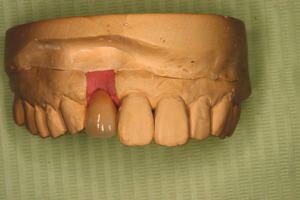

仮の支柱を装着仮の支柱を装着仮の支柱を装着 作業模型上のセラミック上部構造作業模型上のセラミック上部構造作業模型上のセラミック上部構造 術後術後術後

術前術前主訴-バネの目立たない入れ歯にしたい 装着前 義歯の内面義歯の内面義歯の内面(内側に赤いプラスチックが見えますがこれが消耗品で半年に一度くらい交換すれば元の維持が復活します。) 義歯装着後義歯装着後義歯装着後 バネが無いので入れ歯を使っているのが、外からはわからないくらいです。 義歯装着時正面像義歯装着時正面像義歯装着時正面像